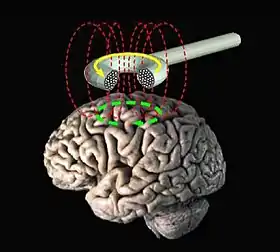

Transcranial magnetic stimulation (schematic diagram) | |

Transcranial magnetic stimulation (TMS) is a noninvasive form of brain stimulation in which a changing magnetic field is used to induce an electric current at a specific area of the brain through electromagnetic induction. An electric pulse generator, or stimulator, is connected to a magnetic coil connected to the scalp. The stimulator generates a changing electric current within the coil which creates a varying magnetic field, inducing a current within a region in the brain itself.[1]: 3 [2]

Procedure

During the procedure, a magnetic coil is positioned at the head of the person receiving the treatment using anatomical landmarks on the skull, in particular the inion and nasion.[13] The coil is then connected to a pulse generator, or stimulator, that delivers electric current to the coil.[2]

TMS uses electromagnetic induction to generate an electric current across the scalp and skull.[22][23] A plastic-enclosed coil of wire is held next to the skull and when activated, produces a varying magnetic field oriented orthogonally to the plane of the coil. The changing magnetic field then induces an electric current in the brain that activates nearby nerve cells in a manner similar to a current applied superficially at the cortical surface.[24]

The magnetic field is about the same strength as magnetic resonance imaging (MRI), and the pulse generally reaches no more than 5 centimeters into the brain unless using a modified coil and technique for deeper stimulation.[23]

Transcranial magnetic stimulation is achieved by quickly discharging current from a large capacitor into a coil to produce pulsed magnetic fields between 2 and 3 Tesla in strength.[25] Directing the magnetic field pulse at a targeted area in the brain causes a localized electrical current which can then either depolarize or hyperpolarize neurons at that site. The induced electric field inside the brain tissue causes a change in transmembrane potentials resulting in depolarization or hyperpolarization of neurons, causing them to be more or less excitable, respectively.[25]